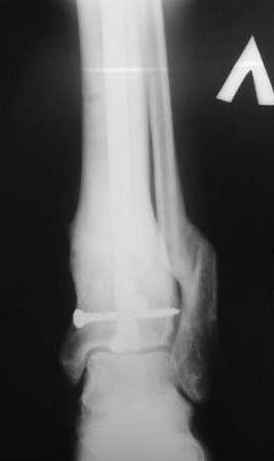

1 - рентгенограмма (прошу прощения за качество) при поступлении;

Произведено ПХО, acute shortening (5 см), фиксация стержневым аппаратом Hoffman.